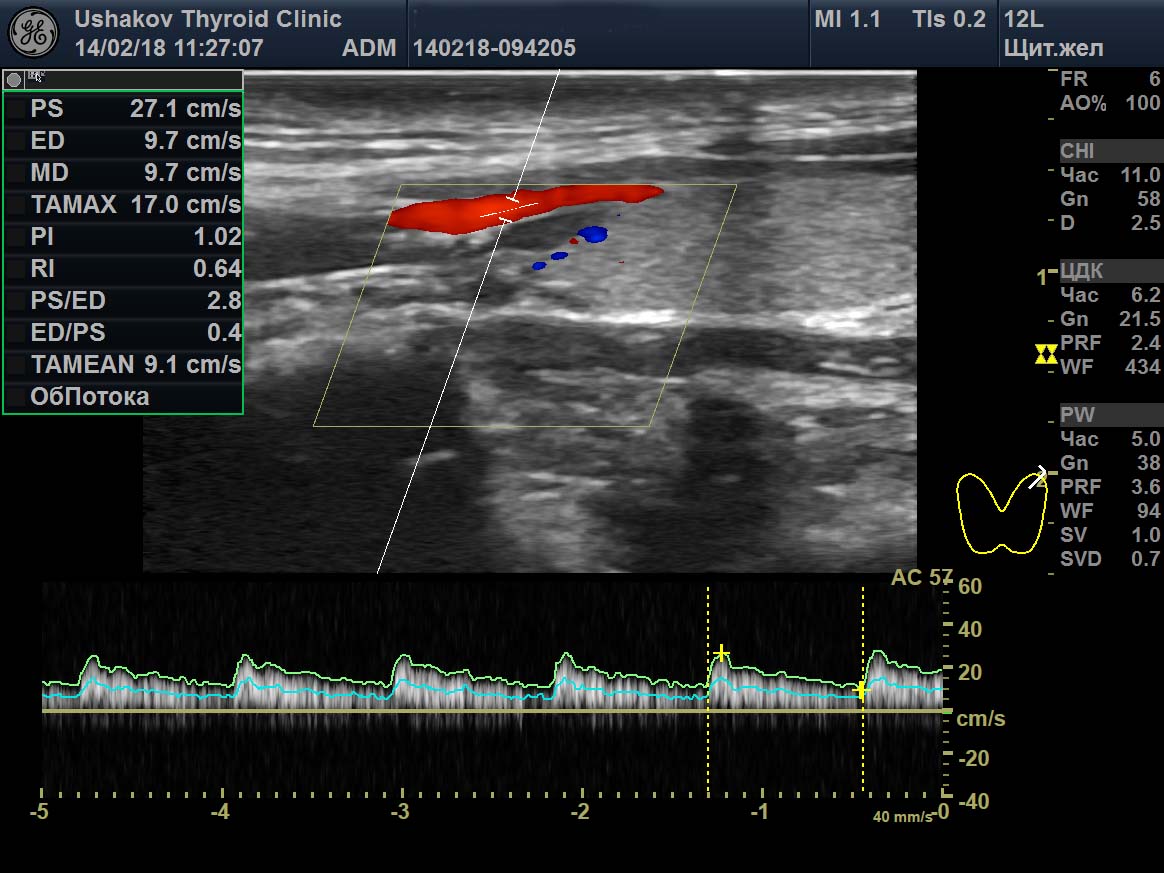

Цдк в узи щитовидной

Цдк в узи щитовидной 110 фото